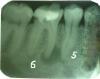

KDaniil Опубликовано 13 февраля, 2008 Поделиться Опубликовано 13 февраля, 2008 Очень нужен совет. Обнаружили кисту. Предлагают в разных клиниках разные варианты! Какой выбрать наилучший? Кому верить? Замучился... 1)удалить половинку 6-го зуба, корень которого поражен и находится в кисте. Пролечить 5-ый зуб т.к. его задевает киста. На оставшуюся часть зуба и на 5-ый нанести коронки и в получившийся пробел установить протез. Или установить имплант. «-» в том что придется стачивать соседние зубы для установки коронки. 2)Удалить 6-ой зуб полностью. Вместе с зубом возможно выйдет и киста. Пролечить 5-ый зуб. При удачном извлечении зуба реплантировать его обратно. Или установить имплант «-» состоит в том что зуб приживется потом намертво (с костью сращивается) и удалить его потом будет большой проблемой (по словам Асии Хамитовны)«-» потеря зуба. Скорее всего при удалении он сломается. 3)Залечить 5 и 6 зубы. Запломбировать каналы. Зделать резекцию корня зуба. С боку в челюсти проделать отверстие, удалить через него кисту и часть корня 6-го зуба, т.к. он поражен кистой.«-» состоит в том что зуб утрачивает свою прежнюю стойкость«-» травматичная операция! 4)Залечить 5 и 6 зубы. Запломбировать каналы.Возможно в 6-ой зуб вставить штифт. Зделать резекцию сбоку в челюсти. Выскрести кисту вокруг корня. Корень оставить на месте.«-» травматичность По каждому варианту вопросы: 1)верхушка второго корня 6-го зуба тоже имеет потемнение. Не начало ли это кисты? Если это будущая киста тогда надо целеком зуб удалять? Если показания 6-го зуба к удалению то почему не надо удалять 5-ый? Ведь его корень тоже затронут кистой? 2)Если ставить имплант будут ли щели между живыми зубами и имплантом? Если нет то образуются ли они потом? Не будет ли скоплений пищи в этих щелях? 3)Если на левом корне тоже маленькая киста то почему левый корень не надо удалять? Почему не надо удалять корень 5-го зуба, ведь он тоже задет кистой? 4)Что вставляется в образовавшуюся полость после удаления кисты? Чем закрывается дырка?? Почему Другие хирурги говорят об удалении зуба либо об удалении корня, если есть способ полностью сохранить зуб? Почему можно не удалять корень который был поражен кистой? Ведь он нездоровый, разве от него не начнет развиваться какой-нибудь нехороший процесс в дальнейшем? Если выскребать только кисту, сохраняя корень, выскребете ли вы маленькую кисту которая на левом корне 6-го зуба?После выскребания кисты корень останется висеть в воздухе?Если киста маленькая, например как на левом корне 6-го зуба, можно ли удалить ее через лечебный канал? (канал клторый пломбируют, где нерв)Если киста прелставляет собой капсулу, то при выскребании она же лопнет и жидкость тяжелее будет выскребать из полости где будет и кровь и корни зубов и черти что там. Там даже будет ничего не видно. Какого размера делать «окошечко» чтобы можно было выскрести эту кисту? Ссылка на комментарий

kromanion Опубликовано 13 февраля, 2008 Поделиться Опубликовано 13 февраля, 2008 Уважаемый Daniil!Считаю,что надо начать с лечения каналов 6-го зуба,пока не трогая "пятерку".Судя по снимку,нерва в зубе уже нет,он неживой,а проходимость каналов хорошая.Обычно лечение таких зубов проходит замечательно,правда,не очень быстро.Результаты лечения должны быть видны на контрольных снимках через 2-3 месяца.Вероятность успеха при консервативном лечении очень высокая Ссылка на комментарий

Большой Зеленый Опубликовано 13 февраля, 2008 Поделиться Опубликовано 13 февраля, 2008 А я бы еще и пятый депульпировал. По моему верхушка у него тоже в полости кисты Очень нужен совет. Обнаружили кисту. Предлагают в разных клиниках разные варианты! Какой выбрать наилучший? Кому верить? Замучился... 1)удалить половинку 6-го зуба, корень которого поражен и находится в кисте. Пролечить 5-ый зуб т.к. его задевает киста. На оставшуюся часть зуба и на 5-ый нанести коронки и в получившийся пробел установить протез. Или установить имплант. «-» в том что придется стачивать соседние зубы для установки коронки. 2)Удалить 6-ой зуб полностью. Вместе с зубом возможно выйдет и киста. Пролечить 5-ый зуб. При удачном извлечении зуба реплантировать его обратно. Или установить имплант «-» состоит в том что зуб приживется потом намертво (с костью сращивается) и удалить его потом будет большой проблемой (по словам Асии Хамитовны) «-» потеря зуба. Скорее всего при удалении он сломается. 3)Залечить 5 и 6 зубы. Запломбировать каналы. Зделать резекцию корня зуба. С боку в челюсти проделать отверстие, удалить через него кисту и часть корня 6-го зуба, т.к. он поражен кистой. «-» состоит в том что зуб утрачивает свою прежнюю стойкость «-» травматичная операция! 4)Залечить 5 и 6 зубы. Запломбировать каналы.Возможно в 6-ой зуб вставить штифт. Зделать резекцию сбоку в челюсти. Выскрести кисту вокруг корня. Корень оставить на месте. «-» травматичность По каждому варианту вопросы: 1)верхушка второго корня 6-го зуба тоже имеет потемнение. Не начало ли это кисты? Если это будущая киста тогда надо целеком зуб удалять? Если показания 6-го зуба к удалению то почему не надо удалять 5-ый? Ведь его корень тоже затронут кистой? 2)Если ставить имплант будут ли щели между живыми зубами и имплантом? Если нет то образуются ли они потом? Не будет ли скоплений пищи в этих щелях? 3)Если на левом корне тоже маленькая киста то почему левый корень не надо удалять? Почему не надо удалять корень 5-го зуба, ведь он тоже задет кистой? 4)Что вставляется в образовавшуюся полость после удаления кисты? Чем закрывается дырка?? Почему Другие хирурги говорят об удалении зуба либо об удалении корня, если есть способ полностью сохранить зуб? Почему можно не удалять корень который был поражен кистой? Ведь он нездоровый, разве от него не начнет развиваться какой-нибудь нехороший процесс в дальнейшем? Если выскребать только кисту, сохраняя корень, выскребете ли вы маленькую кисту которая на левом корне 6-го зуба? После выскребания кисты корень останется висеть в воздухе? Если киста маленькая, например как на левом корне 6-го зуба, можно ли удалить ее через лечебный канал? (канал клторый пломбируют, где нерв) Если киста прелставляет собой капсулу, то при выскребании она же лопнет и жидкость тяжелее будет выскребать из полости где будет и кровь и корни зубов и черти что там. Там даже будет ничего не видно. Какого размера делать «окошечко» чтобы можно было выскрести эту кисту? Вы наверное слабо представляете что такое киста. это уже полость в челюсти т.е. пустота .После устранения причины .полость кисты заполнится костной тканью.. Ссылка на комментарий

KDaniil Опубликовано 14 февраля, 2008 Автор Поделиться Опубликовано 14 февраля, 2008 мне 30 лет. Вчера ходил к врачу у которого решил лечиться. Предварительно распечатав ваши советы, дал почитать ей. Она сказала что советы дельные. Можно и поробовать полечить. Решили сделать так: пока прочистить каналы 6-го зуба (в любом случае это надо делать). Прочистили, там столько черноты было! и неприятный запах. Положили какоето лекарство туда..Кстати сделали снимок еще один. На нем хорошо видно что и 5-ый зуб вовлечён в кисту.Сегодня пойду снимать лекарство с 6-го, пломбировать его и лечить 5-ый. А завтра наверно резекцию делать. Но корень решили не трогать. Врач сказала что сейчас много современных медикаментов котороые позволяют прочистить полость и обработать корень зуба. Возможность рецидива минимальна.Не знаю так ли это.. Ещё вчера врач прощупала пальцами обе стороны челюсти и сказала что там где киста, чувствуется, что это место немножко выпуклое и мягкое.. сказала что похоже что костная ткань "разъелась" почти до краяне знаю наскольок травматична будет резекция.. врач сказала что нервный канал идет далеко от зубов.. нерв не заденем. Ссылка на комментарий

Dr. Smile Опубликовано 14 февраля, 2008 Поделиться Опубликовано 14 февраля, 2008 Кстати сделали снимок еще один. На нем хорошо видно что и 5-ый зуб вовлечён в кисту. Сегодня пойду снимать лекарство с 6-го, пломбировать его и лечить 5-ый. А завтра наверно резекцию делать. Перед тем, как лечить пятый, очень желательно, чтобы доктор проверил его, живой ли он - это легко сделать холодной водой или льдом, или, как вариант, разогретым инструментом (или гуттаперчей). Вполне возможно, что 5-ка живая, в этом случае ее лечить не надо. Ссылка на комментарий

KDaniil Опубликовано 15 февраля, 2008 Автор Поделиться Опубликовано 15 февраля, 2008 5-ку уже пролечили вчера. в 6-ку установили штифт и запломбировали. В ходе лечения делали снимки.После лечения стало видно что в верхушку заднего кореня 6-ки пломба дошла до окнца и даже прошла в маленькое потемнение около корня(такая белая субстанция просматривается). Врач сказала что именно это небольшое количество попавшее в зарождавшуюся кисту постепенно вылечит ее.в переднем корен тоже самое. В кисту (с верхушки переднего корня 6-ки) попало чтото (наверное часть пломбы, оно же и как лекарство). Но его не достоточно для залечивания кисты. Кисту всеравно удалять..И еще у меня ощущение что врач, сказав что корень оставит, а кисту удалит - лукавит. Наверно чтоб не пугать меня. Под анастезией всеравно ничего не чувствуется.. что она там будет удалять.Корень наверное нельзя оставлять Ссылка на комментарий